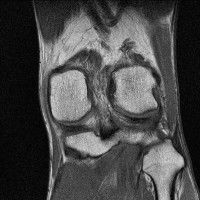

무릎 mri 간단히 봐주실 수 있으시나요 ㅠㅠ

안녕하세요 8년전 십자인대 수술하고 최근 무리한 운동에 무릎 불편감이 생겨서

mri 찍었습니다.

진단결과는 첫 찍은 병원에서 활액막염 이라는 진단을 받았습니다. 혹시 봐주실 수 있으실까요?

올라온 MRI가 단편적이라서 정확한 진단에 어려움이 있지만 십자인대에는 큰 이상이 있지는 않은것 같으며, 무릎관절내 물이 있는 것으로 보아 활액막염의 진단이 맞을 것 같습니다.

하지만 단편적인 영상이기 때문에 촬영병원에서 정확한 판독지 등을 받으시는 것이 좋겠습니다.